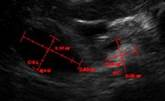

9.2.1. Measurements

To conduct a measurement, follow the instructions below:

3.     Select the measurement-of-interest and then draw the measurement on the image within the viewer.

•     CRL – Crown Rump Length

•     BPD – Biparietal diameter

•     HC – Head Circumference

•     AC – Abdomen Circumference

•     FL – Femur length

The approximated gestational age (GA) per measurement and the average GA will be calculated after any measurement is conducted. Once all five measurements have been conducted, the estimated fetal weight (EFW) value will also be calculated. The estimated delivery date (EDD) will be calculated: